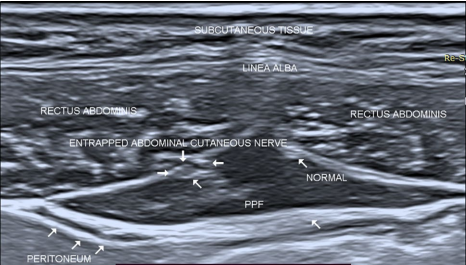

Spectrum of abdominal anterior cutaneous nerve entrapment syndrome (ACNES) with successful management: a case report

Abdominal pain is a common symptom with a spectrum of causes. Anterior cutaneous nerve entrapment syndrome (ACNES) is a commonly overlooked and underdiagnosed cause for anterior abdominal pain. Among the patients of chronic abdominal wall pain, the incidence of ACNES is 10–30% and the most common cause is nerve entrapment at the lateral border of the rectus muscle. We describe two cases covering varied location of entrapment, one at the medial border of rectus and another at lateral border explaining the need of ultrasound for successful management of both. This case report illustrates the difficulty of making this diagnosis, utility of ultrasound and a brief review of literature.